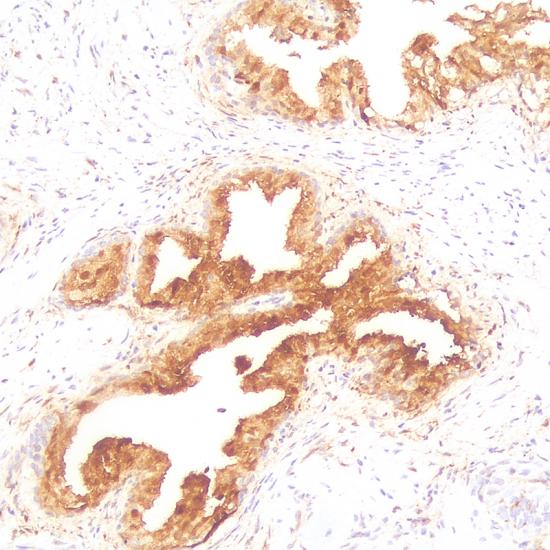

Galectin-3

Galectin-3抗體試劑(免疫組織化學) 閩廈械備20180094號

• 陽性部位:

細胞漿/細胞核

• 陽性對照:

甲狀腺癌

半乳凝素-3(Galectin-3)是β-半乳糖結合凝集素家族的一員。Galectin-3可與CK19聯(lián)合用于甲狀腺乳頭狀腺癌的診斷,是間變性大細胞淋巴瘤很有效的標記,還可以作為腫瘤惡化程度的一個參考指標。